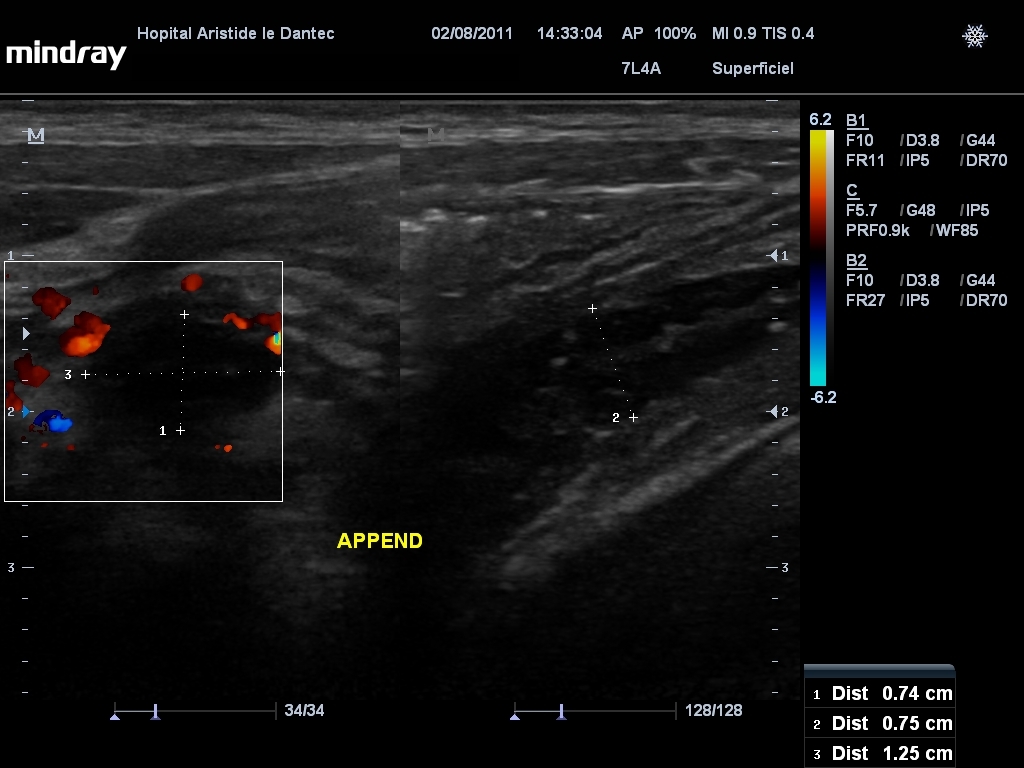

R6opere le 19 novembre pour appendicectomie et fermeture de la fistule. Admin june 26, 2019 no comments. Ultrasound is the first investigation advised to evaluate a suspected appendicular pathology.

The computed tomography performed in 29.4%, confirmed. Operation suivie de fistule caecale. Intervention en urgence ou différée: À propos d’une série de 27 cas dans la clinique chirurgicale de l’hôpital aristide le dantec appendicular plastron:

Dans notre milieu, il s'agit d'un cas confirmé de mucocèle appendiculaire sur 874 d'appendicectomies réalisées dans le service.